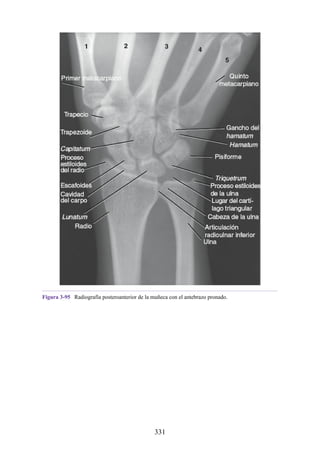

lo largo de las líneas de estrés mecánico.

La vaina sinovial es una bolsa tubular que envuelve el tendón (véase fig. 1-